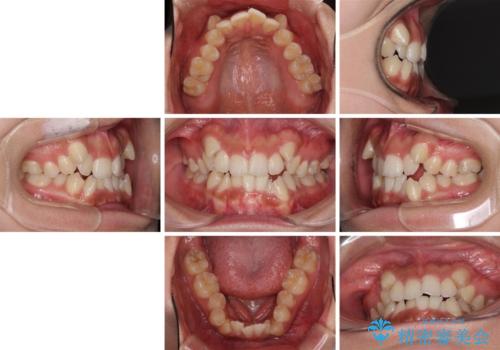

- 顕著な八重歯が気になるとのことで来院された患者様です。

インビザラインでの治療を希望されましたが、インビザライン単独では困難と判断されたため、補助装置や一部ワイヤー装置を用いて行うこととしました。

叢生が強いため、上下左右第一小臼歯4本を抜歯することとしました。